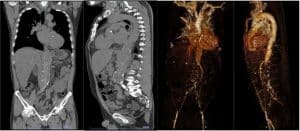

The patient was initially given paracetamol 1 gram, then tramadol 50 mg TIV, eventually nalbuphine 2 mg TIV because of intractable pain. At that time, the emergency physician was considering myositis vs. vascular occlusion. Routine labs were done. ECG revealed sinus rhythm, T wave inversion at V5-6, AVL, and lead 1. CBC showed leukocytosis with neutrophilic predominance. Chest x-ray revealed progression in the degree of mild pulmonary congestive changes as well as suspicion of concomitant pneumonia in the right lower lobe. Lumbosacral x-ray revealed a decompression deformity T 11. FPA supine and upright results were segmental adynamic ileus, which prompted consideration of hepatomegaly and lumbar osteophytosis. Hence, the patient was referred to Vascular (IM service) and TCVS for further evaluation and management. A Stat AV duplex scan was advised but not available in the ED. Hence abdominal CT scan (Figure 2 and Figure 3) with contrast and CT aortogram was performed. Tomography revealed atherosclerotic thoraco-abdominal aorta with mural thrombus formation, aneurysmal dilatation at the level of the ascending aorta, transverse arch, celiac artery, superior mesenteric artery, and renal artery, no dissection or contrast extravasation. Thus, the patient was then administered a heparin drip 10, 000 units in 100 cc to run for 10 cc/hr (18 units/kg/hr). Cefepime 2 g TIV as a loading dose for pneumonia was given as well.

Figure 3: Abdominal CT scan and CT aortogram (coronal and sagittal view)

Imaging is an important tool in determining the location of the possible obstruction. In this case, thromboembolism was located at thoraco-abdominal aorta which led to an aneurysmal dilatation at the level of the ascending aorta, transverse arch, celiac artery, superior mesenteric and renal artery. These signs manifest as an abdominal pain in the patient.